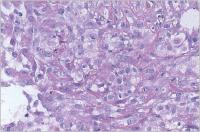

Fallbericht: Ein ungewöhnlicher Fall eines solitären Knotens in der Brust als Erstmanifestation eines anaplastischen Schilddrüsenkarzinoms